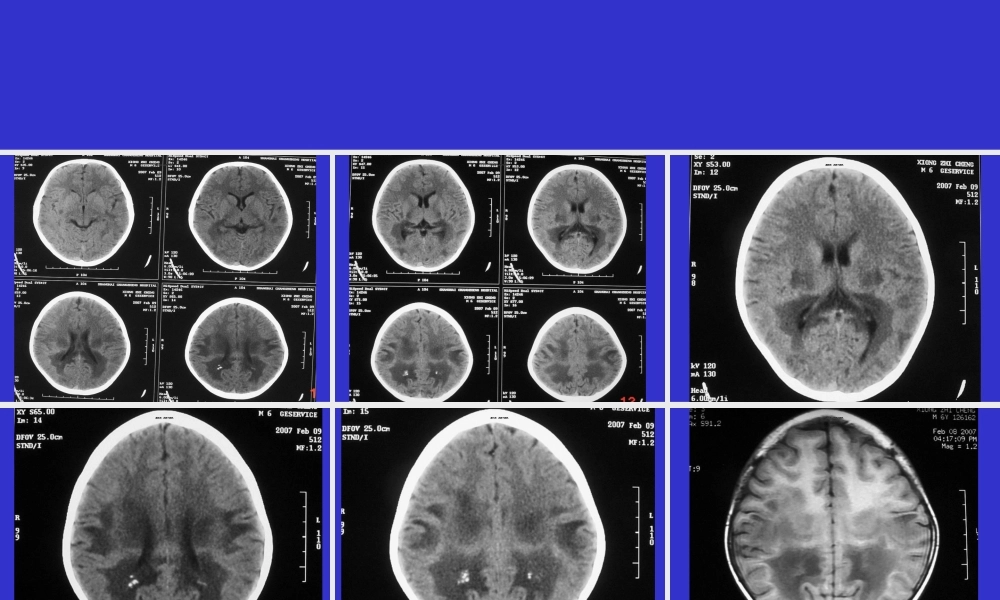

常见(chánjiàn)ɡ脑白质病梅河口市新华医院第一页,共四十四页。第一页,共四十四页。第二页,共四十四页。第二页,共四十四页。第三页,共四十四页。第三页,共四十四页。第四页,共四十四页。第四页,共四十四页。第五页,共四十四页。第五页,共四十四页。第六页,共四十四页。第六页,共四十四页。第七页,共四十四页。第七页,共四十四页。第八页,共四十四页。第八页,共四十四页。第九页,共四十四页。第九页,共四十四页。第十页,共四十四页。第十页,共四十四页。第十一页,共四十四页。第十一页,共四十四页。第十二页,共四十四页。第十二页,共四十四页。第十三页,共四十四页。第十三页,共四十四页。第十四页,共四十四页。第十四页,共四十四页。第十五页,共四十四页。第十五页,共四十四页。第十六页,共四十四页。第十六页,共四十四页。第十七页,共四十四页。第十七页,共四十四页。第十八页,共四十四页。第十八页,共四十四页。第十九页,共四十四页。第十九页,共四十四页。诊断(zhěnduàn):肾上腺脑白质营养不良肾上腺脑白质营养不良(Adrenoleukodystrophy,ALD),又称阿狄森-弥漫性脑硬化症(Addison-SchilderDisease)、黑皮脑白质营养不良、……等、1912年Schilder首次报道,Blaw于1964年正式命名为肾上腺脑白质营养不良。该病是脑白质营养不良中最常见的一种,通常是指一组X染色体连锁(liánsuǒ)隐性遗传的疾病(简称X-ALD),但广义上也包括一组常染色体隐性遗传的ALD(简称为A-ALD,automosalALD),即指新生儿ALD。第二十页,共四十四页。第二十页,共四十四页。病理(bìnglǐ)•目前一般认为由于溶酶体过氧化酶的缺乏,导致极长链脂肪酸在细胞异常堆积,特别在脑白质和肾上腺皮质内的沉积、导致脑白质和肾上腺皮质的破坏,从而产生特征性的脑白质和肾上腺皮质损害的临床(línchuánɡ)症状。第二十一页,共四十四页。第二十一页,共四十四页。脑皮质厚度稍薄或正常。主要病理改变在白质,呈弥漫性白质减少致脑室(nǎoshì)中、重度扩大、脑沟增宽。顶、枕、颞叶等处脑向质内出现对称性髓鞘脱失改变、可有显著胶质增生。病变常侵及胼胝体,主要在压部。额叶的脱髓鞘发生稍迟且多不对称。小脑、脑干也可以有脱髓鞘发生,内囊、外囊、锥体束等可见连续性髓鞘脱失改变。並可出现鈣质沆积,有时很广泛而显著。第二十二页,共四十四页。第二十二页,共四十四页。这些髓鞘脱失区从外向内可分为三个病理(bìnglǐ)...